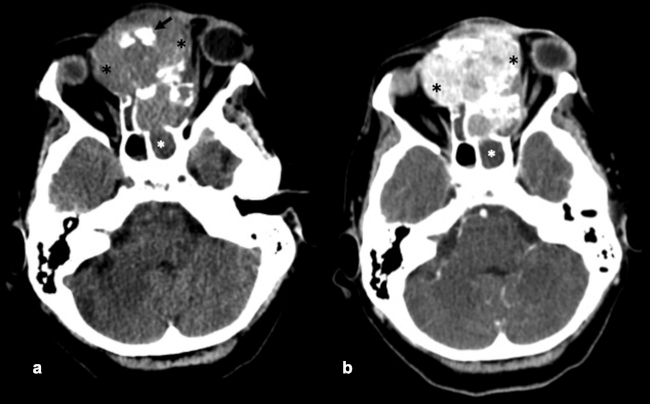

La TC de corte fino (espesor de corte de 1 mm) con reconstrucciones en plano coronal y sagital, es la mejor prueba de imagen inicial para el estudio del NBO. En la TC, aparece como una masa homogénea de tejido blando en la bóveda nasal con realce moderado y uniforme (►Figs.1y2). Se pueden encontrar calcificaciones punteadas dispersas (►Figs.2,3,4,5a,6).50 El valor principal de la TC es una mejor definición de la afectación ósea en comparación con la RM. La TC ayuda a evaluar la erosión ósea de la placa cribiforme, la fóvea etmoidal y la lámina papirácea (►Figs.1,2,3,4,5a,8). Sin embargo, la remodelación ósea sin erosión puede presentarse en algunos casos debido a su patrón de crecimiento indolente.3,35,49 Los estudios de TC generalmente revelan un patrón lítico y muy raramente hiperostosis dominante que simula displasia fibrosa.51 La TC también es útil para evaluar la presencia de metástasis regionales en cuello y a distancia.52,53

La RM es la prueba de imagen de elección para evaluar los detalles de la extensión y la estadificación locorregional del tumor. La RM es superior a la TC para determinar el grado de afectación del tejido blando (►Fig. 9) con una mejor evaluación de la afectación intracraneal (►Figs.10,11,12,13,14), orbital (►Figs.14y15), de la base del cráneo y la invasión perineural.53,54 La RM tiene un valor añadido para distinguir la afectación dural de la del parénquima cerebral (►Fig. 12).55 En la RM, el NBO aparece hipointenso respecto a la sustancia gris en imágenes ponderadas en T1 y de isointenso a hiperintenso en las imágenes ponderadas en T2 (►Figs.10,11,12,13,14,15).56 Muestra un realce homogéneo, excepto en áreas con hemorragia o necrosis. Además, permite diferenciar las secreciones retenidas del tumor, al ser estas hiperintensas ponderadas en T2.53,55 Los hallazgos de imágenes clásicos incluyen una masa “en forma de mancuerna” que se extiende a través de la placa cribiforme (►Fig. 12), con la parte estrecha a nivel de la placa. Los quistes tumorales periféricos (►Figs.5b,12,14,16) y las calcificaciones moteadas son bastante característicos de NBO.1